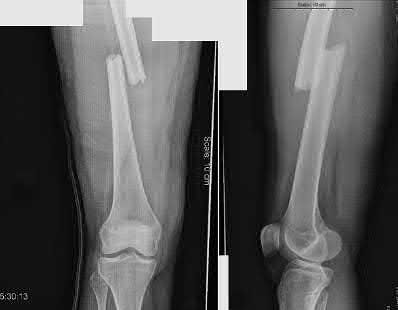

What is the most common type of malalignment after intramedullary nailing of distal 1/3 extra-articular tibia fractures using a infrapatellar approach when compared with plating?

The most common type of malalignment after intramedullary nailing of distal 1/3 extra-articular tibia fractures using an infrapatellar approach when compared with plating is valgus malalignment.

Fixation of distal one-third tibial shaft fractures can be successfully treated with either intramedullary nailing or plating. The literature describes advantages and disadvantages to both approaches, however intramedullary nailing has been shown to lead to increased rates of valgus malunion. Recent studies have shown that using a suprapatellar approach may decrease the incidence of valgus malalignement.

Vallier et al performed a randomized prospective study to compare plate and nail stabilization for distal tibia shaft fractures by assessing complications and secondary procedures. One-hundred and four patients were randomized to either reamed intramedullary nailing, or medial distal tibia plate fixation.

Primary angular malalignment was identified in 17 patients (16.3%). This included four patients treated with tibial plating (8.3%) and 13 patients treated with nails (23%, P = 0.02). Eight of these (7.7% of all patients) had malalignment between 6° and 10° of angulation. Valgus was the most common

angular deformity, accounting for 70% of angular deformity cases.

Avilucea et al. looked at the immediate postoperative alignment of distal tibia fractures (within 5 cm of the tibial plafond) treated with suprapatellar intramedullary nail (IMN) insertion compared with the infrapatellar technique. They found primary angular malalignment of ≥5 degrees occurred in 35 (26.1%) patients with infrapatellar IMN insertion and in 5 (3.8%) patients who underwent suprapatellar IMN insertion. They conclude suprapatellar IMN technique results in a significantly lower rate of malalignment compared with the infrapatellar IMN technique.

Answer 1, 3,4, and 5: Vallier et al. found that valgus was the most common angular deformity.